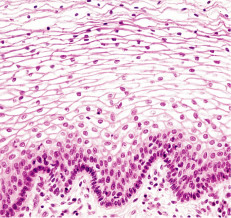

cartilage

rigid, providing protections, frameworks attachments and support